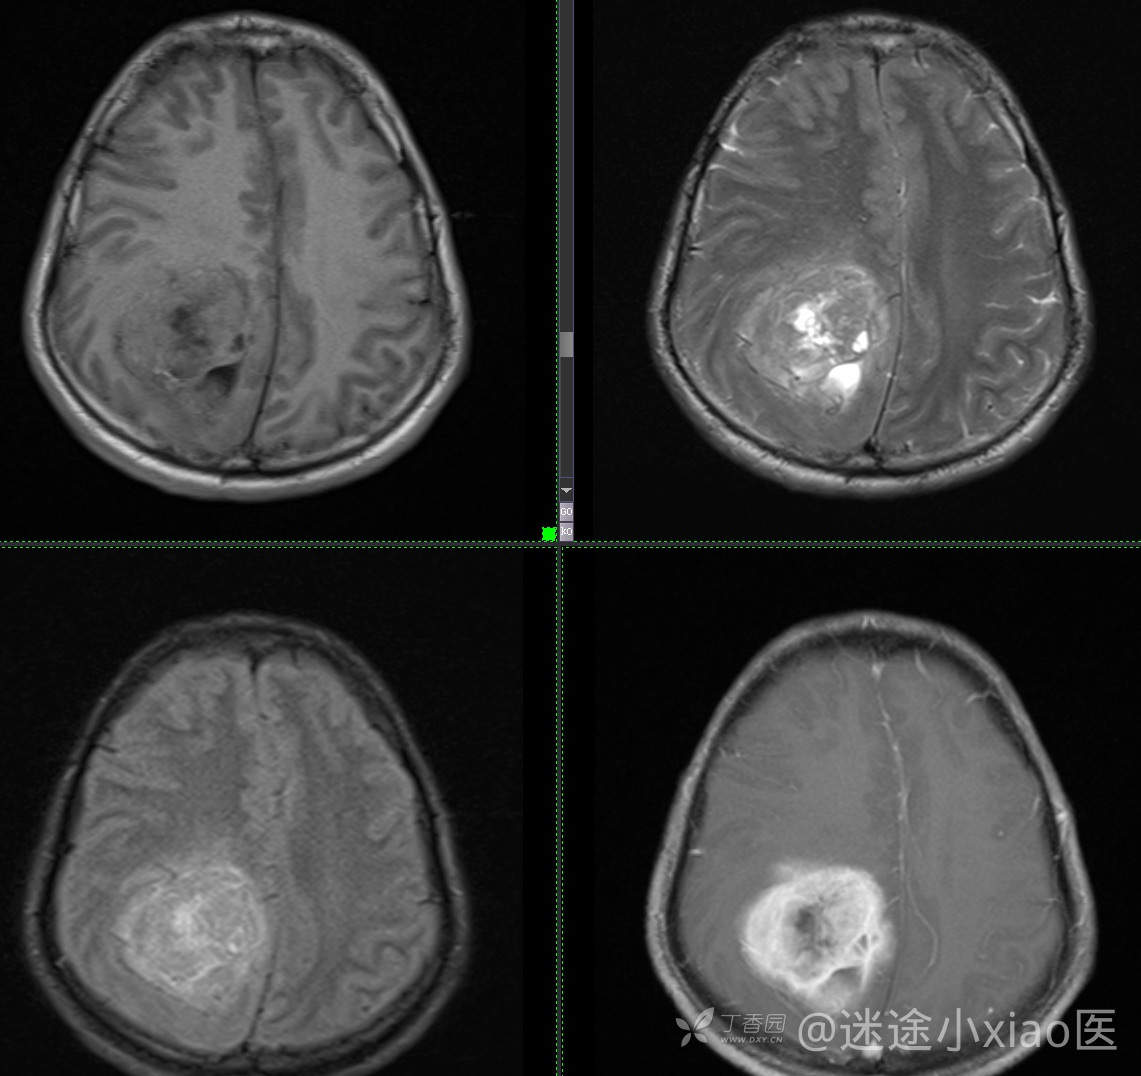

患者年龄:43

患者性别:男

简要病史:头痛3月余,查体无殊